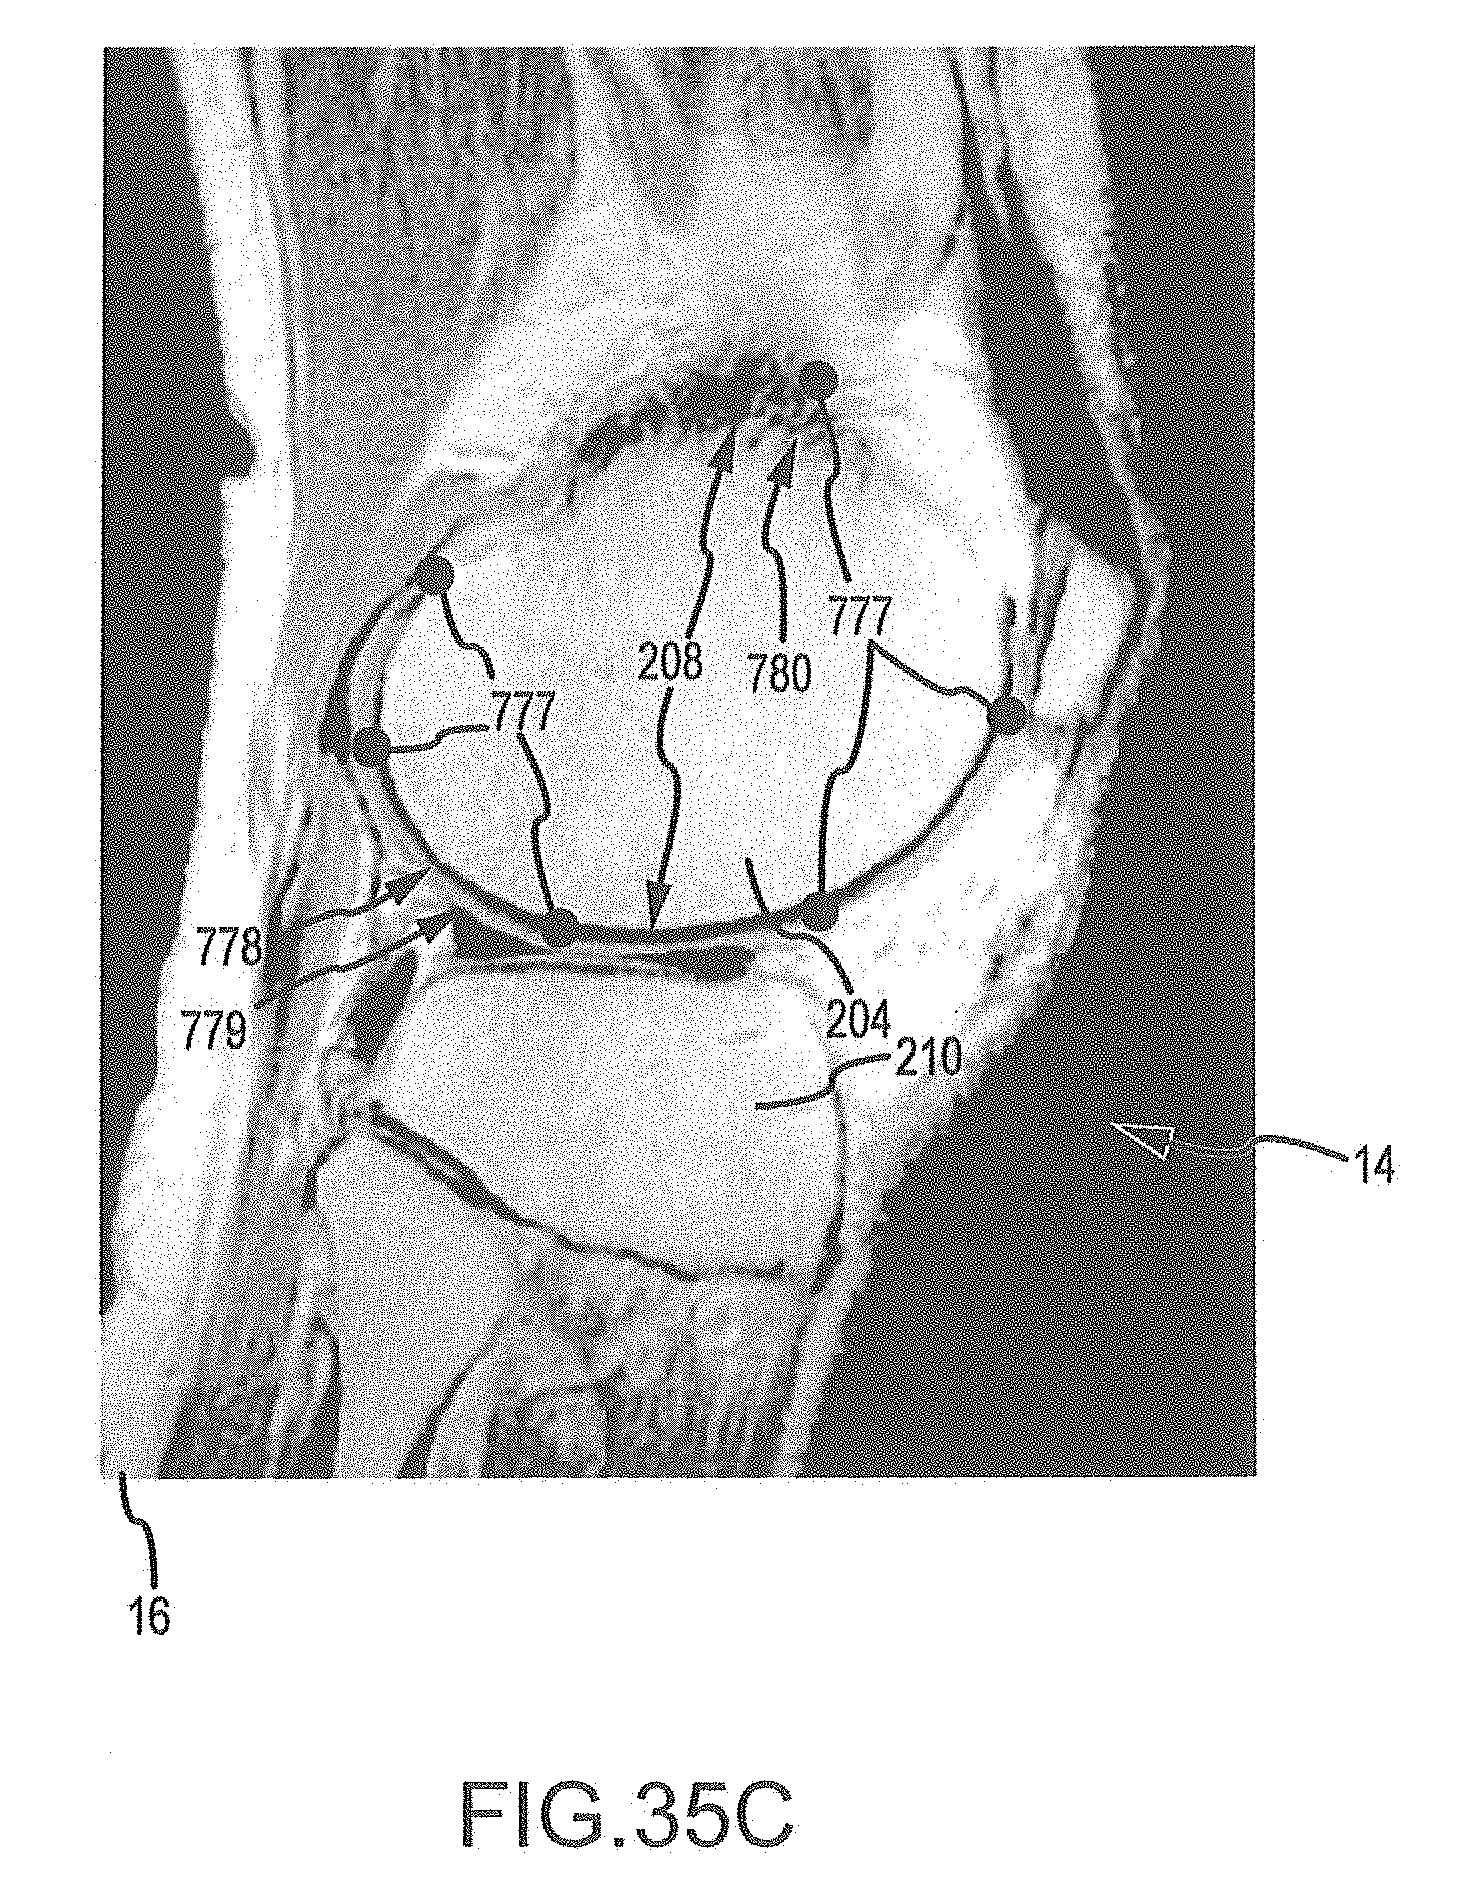

FIGS. 35A-35H are a series of sagittal image slices wherein landmarks have been placed according the process of FIG. 34.

The imager 8 typically generates a plurality of image slices 16 via repetitive imaging operations. Depending on whether the imager 8 is a MRI or CT imager, each image slice will be a MRI or CT slice. As shown in FIG. 2A, the image slice may depict the cancellous bone 200, the cortical bone 202 surrounding the cancellous bone, and the articular cartilage lining portions of the cortical bone 202 of an object of interest of a joint, e.g., a femur 204 in a patient's knee joint 14. The image may further depict the cancellous bone 206, the cortical bone 208 of another object of interest in the joint, e.g., a tibia 210 of the knee joint 14. In one embodiment, each image slice 16 may be a two-millimeter 2D image slice.